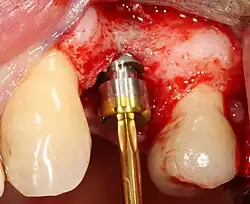

Основная операция по имплантации

Разборный имплантат состоит из непосредственно имплантата и надстройки (супраструктуры), именуемой абатментом. Такой имплантат может быть установлен по одно- и двухэтапному протоколу. Двухэтапный протокол подразумевает полное погружение имплантата и накрывание его слизистой оболочкой, в результате чего исключается любой контакт имплантата с полостью рта — эта процедура называется первым этапом дентальной имплантации. Второй этап заключается в установке какой-либо надстройки (супраструктуры) — это может быть как формирователь десны, так и абатмент с временной коронкой или другим видом протезной конструкции. После какого промежутка времени будет выполнен второй этап обычно решает имплантолог, опираясь на данные о качестве костной ткани, возраст и общее состояние пациента, а также свой клинический опыт. Классические сроки составляют 4—6 месяцев, однако последнее время существует тенденция к сокращению сроков ожидания до 2,5—3 месяцев. Это связано с лучшим пониманием процесса остеоинтеграции, а также оптимизацией макродизайна и микрохарактеристик поверхности имплантатов.